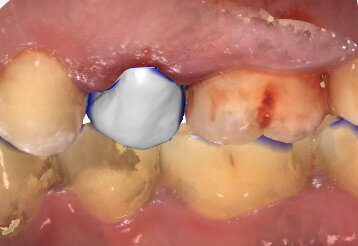

3.8 mm per un impianto di 4.1 mm. La qualità dell’osso non richiedeva maschiatura e dovendo aumentare la stabilità primaria, al fine di determinarne il pieno successo, abbiamo inserito l’impianto in successione a fine preparazione. Al termine dell’inserimento si rileva un’impronta secondo tecnica digitale con uno scanner intraorale e previa modellazione Cad/Cam si esegue una corona in Telio in modalità Chairside (Fig. 3), replicando il contorno originario dell’alveolo post-estrattivo e consentendo di creare un sigillo al fine di favorire la stabilizzazione del coagulo ematico con un supporto meccanico immediato ai tessuti molli circostanti6. Il ruolo svolto dal provvisorio soddisfa la componente estetica, con il condizionamento dei tessetti molli e l’eventuale mantenimento di biomateriali inseriti tra l’alveolo e l’impianto (Fig. 4).

Fig. 3_Impronta digitale post-operatoria. Si evidenzia la realizzazione di una corona provvisoria immediata.

Fig. 4_Posizionamento di un provvisorio in Telio realizzato secondo tecnica chairside.